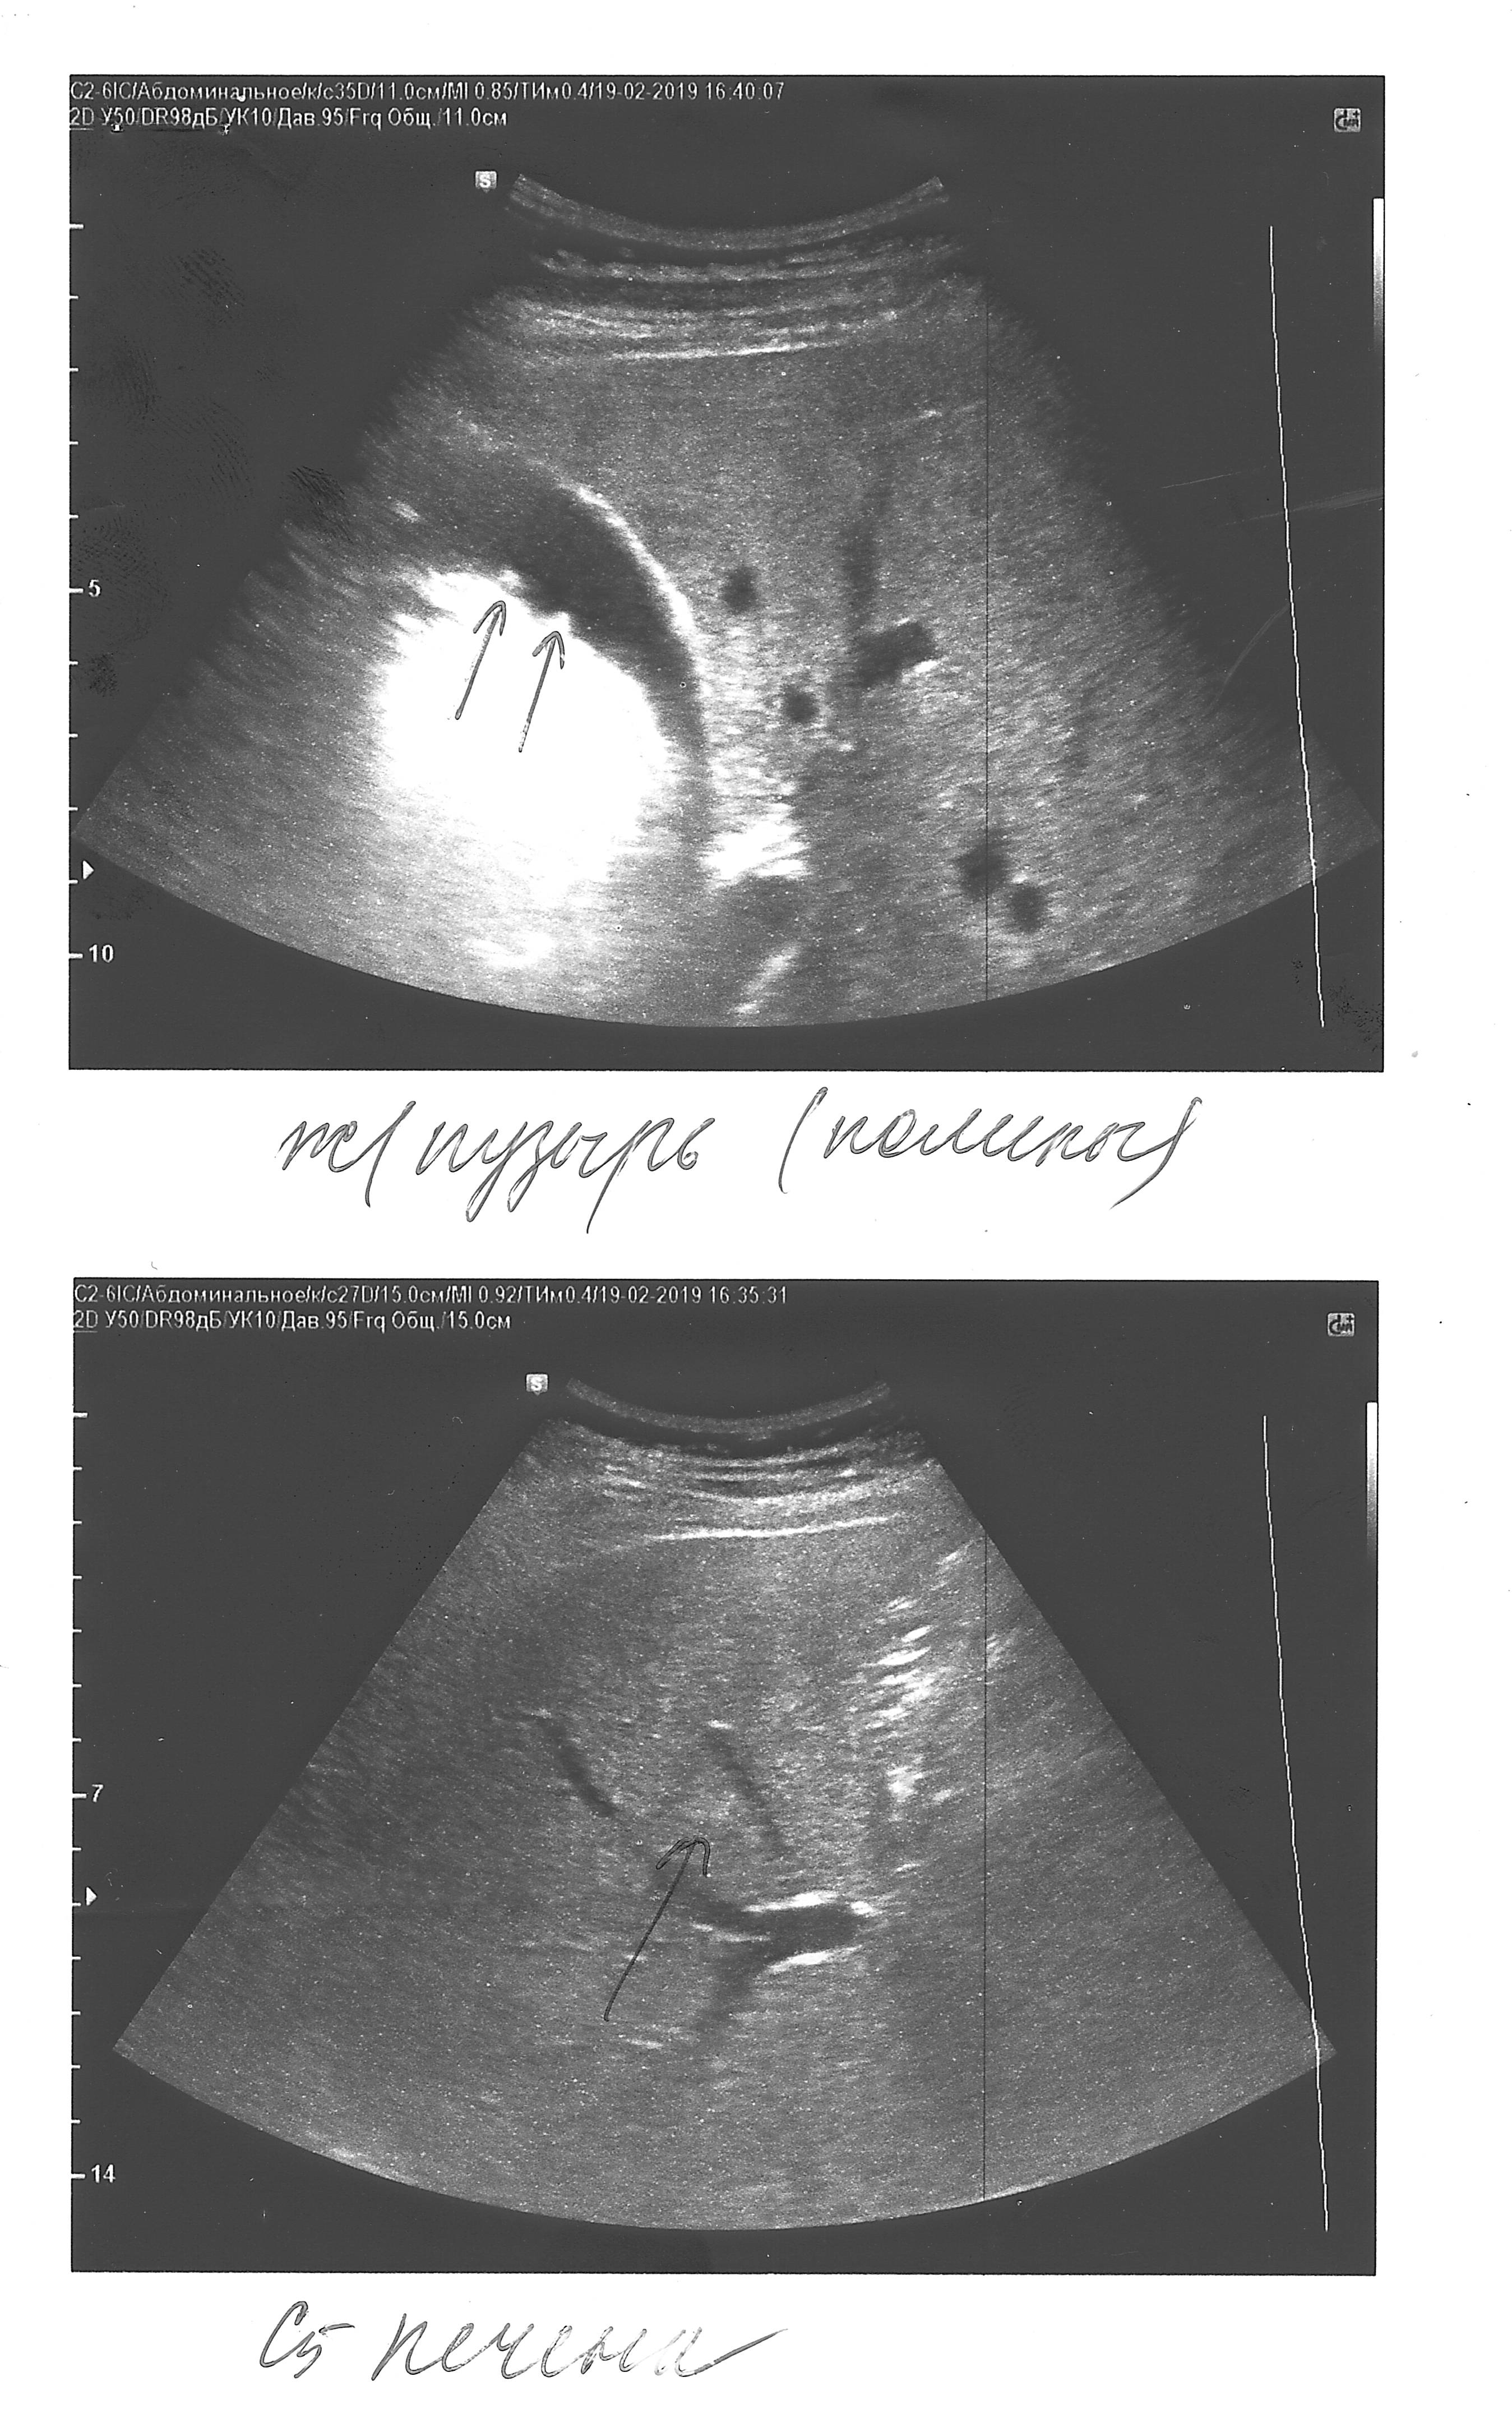

5) консультация врачей на счет полипов в желчном (обычно по результатам УЗИ должны указывать их размеры, есть ли кровоток в основании и проч.)